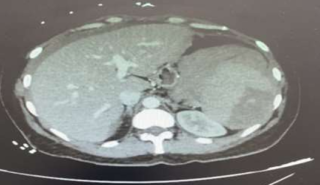

La conduite à tenir a consisté à réaliser une embolisation par coils de l’artère splénique dans sa partie proximale sous anesthésie locale (Figure 2), accompagnée d’une transfusion sanguine.

Figure 2 : Scanner abdominal sans injection (C-) en coupe axiale : visualisation d’un coil à l’origine de l’artère splénique.

Les suites post-opératoires ont été simples. Un angioscanner de contrôle réalisé le lendemain a montré : des signes d’embolisation splénique avec un infarctus d’environ 75 % de la rate. Aucune augmentation notable de l’hématome sous-capsulaire ou de l’hémopéritoine diffus n’a été observée.